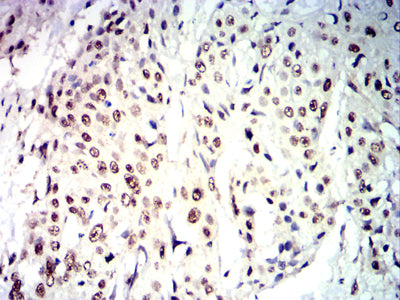

Immunohistochemical analysis of paraffin-embedded human esophageal cancer tissues using CDX2 mouse mAb with DAB staining.